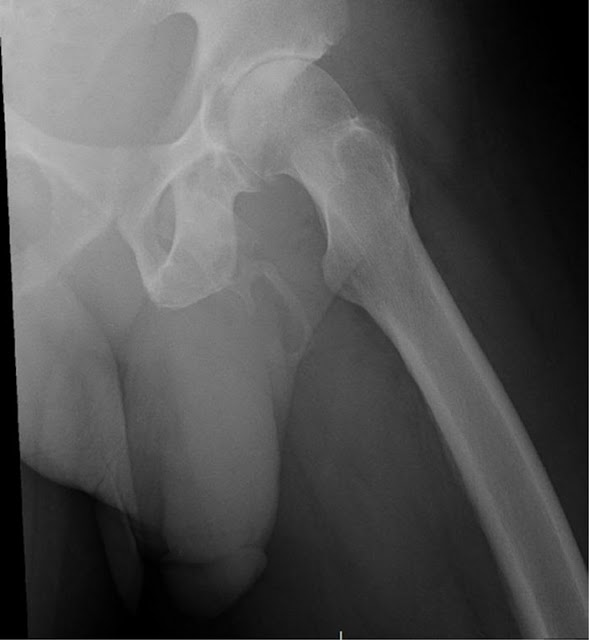

The doctors found this case extremely rare when they performed a radiograph of the pelvis, in order to look for signs of bone fracture. But instead, they spotted a bone-like calcification in a most unexpected place ...

Calcium salts have accumulated in soft tissues and have hardened to form an "extended plaque" along the penis stem, as you can see on the radiograph below: